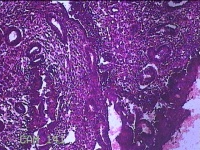

子宫腔赘生物(大)

性别

女

年龄

38岁

临床诊断

子宫内膜息肉;子宫异常出血

一般病史

月经量多数年,发现宫腔占位1个月。

标本名称

大体所见

灰白暗红色不规则肿物2.7x1.8x0.8cm一堆,切开肿物呈实性,切面灰白暗红色,质软。

图3

有那么点像子宫内膜息肉,片子这个效果,辩认起来非常困难。